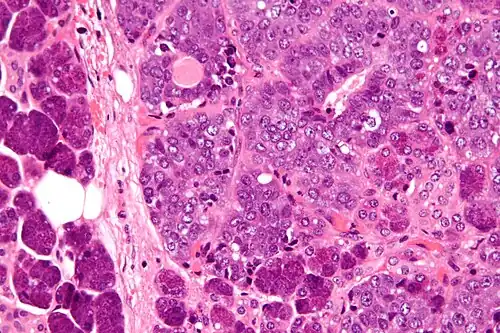

Histologicamente, o CEM se organiza com uma bicamada de células luminais com citoplasma eosinofílico, e células mioepiteliais de citoplasma claro e ricas em glicogênio na periferia.[1] Alguns outros subtipos arquiteturais podem ser vistos, como tubular, glandular, sólido, cístico ou papilar, e a proporção entre células epiteliais e mioepiteliais pode variar.[1][4] A metaplasia escamosa, sebácea ou em corpos de Verocay pode ser encontrada.[1][5]

Em casos raros pode se observar outras variantes morfológicas, como a oncocítica (normalmente de arquitetura papilar, com calcificações e citoplasma granular, que afeta pacientes mais velhos) ou apócrina (arquitetura cribiforme ou sólida, com células ductais intensamente eosinofílicas e morfologia apócrina, produzindo secreção luminal; essas células são positivas para receptor de andrógeno e GCDFP-15).[1][6][7]

Cerca de 20% dos CEM possuem transformação em alto grau, usualmente do componente epitelial, que sugere pior prognóstico: nesses tumores, há proliferação de células atípicas em lençol e ilhotas sólidas, com aumento do número de mitoses e necrose.[1][8]